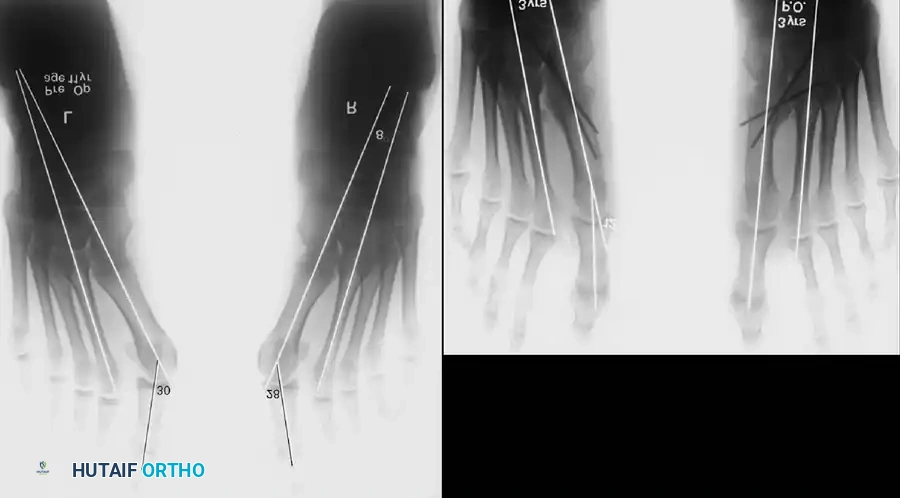

Hallux valgus (lateral deviation of the great toe) is not a single disorder, as the name implies, but a complex deformity of the fi rst ray that frequently is accompanied by deformity and symptoms in the lesser toes (Fig. 78-1). Often the angle between the fi rst and second metatarsals is more than the 8 to 9 degrees usually considered to be the upper limits of normal. The valgus angle of the fi rst metatarsophalangeal joint also is more than the 15 to 20 degrees considered to be the upper limits of normal (Fig. 78-2). If the valgus angle of the fi rst metatarsophalangeal joint exceeds 30 to 35 degrees, pronation of the great toe usually results. With this abnormal rotation, the abductor hallucis, which is normally plantar to the fl exion-extension axis of the fi rst metatarsophalangeal joint, moves further plantarward (Fig. 78-3). In this case, the only restraining medial structure is the medial capsular ligament with its capsulosesamoid portion (inserting into the base of the proximal phalanx) (Fig. 78-4) and capsulophalangeal portion (inserting into the plantar plate). The adductor hallucis, which is unopposed by the abductor hallucis, pulls the great toe further into valgus, stretching the medial capsular ligament (particularly the capsulosesamoid), attenuating this structure, and allowing the metatarsal head to drift medially from the sesamoids. In addition, the fl exor hallucis brevis, fl exor hallucis longus, adductor hallucis, and extensor hallucis longus increase the valgus moment at the metatarsophalangeal joint, further deforming the fi rst ray. The deep transverse intermetatarsal ligament runs between the plantar plates at the metatarsophalangeal joints and does not insert into bone on the adjacent sides of the metatarsal heads. Finally, the sesamoid ridge on the plantar surface of the fi rst metatarsal head (the crista) fl attens because of pressure (abutment) from the tibial sesamoid (Fig. 78-5). With this restraint lost, the fi bular sesamoid displaces partially or completely into the fi rst intermetatarsal space (see Fig. 78-2). In this situation, the patient is bearing less weight on the fi rst ray and more on the lesser metatarsal heads, increasing the likelihood of transfer metatarsalgia, callosities, and stress fracture of a lesser metatarsal.

Fig. 78-2 Hallux valgus complex. Note increase in intermetatarsal angle, lateral dislocation of sesamoids, subluxation of fi rst metatarsophalangeal joint (leaving metatarsal head uncovered), and pronation of great toe associated with marked hallux valgus.

Inadequate vascularity or sensibility should be investigated thoroughly before bunion surgery is considered. In addition, the position of the articular surface of the metatarsal head in relation to the longitudinal axis of the fi rst metatarsal should be determined (Fig. 78-8). Standard preoperative radiographs should include standing dorsoplantar and lateral views, a nonstanding lateral oblique view, and axial sesamoid views (Fig. 78-9). The hallux valgus angle and the fi rst-second intermetatarsal angle should fi rst be drawn on the standing dorsoplantar view by bisecting the shafts of the bones (Fig. 78-10), with an awareness of the normal ranges. These angles are most frequently cited as guidelines for treatment decisions, but Donnelly et al. reported that interobserver measurements of the hallux valgus angle varied by approximately 6 degrees and of the intermetatarsal angle by 4 degrees. They cautioned that potential errors in measurement should be considered when these parameters are used to make treatment decisions. The hallux valgus interphalangeus angle and any evidence of degenerative arthritic changes at the fi rst metatarsophalangeal or metatarsocuneiform joints should be documented. Oddities may be present and, if overlooked, may compromise a technically well-done procedure. Mann emphasized that the presence of an os inter-

Fig. 78-8 A, Determination of position of articular surface of metatarsal head in relation to longitudinal axis of fi rst metatarsal. B, Measurement of distal metatarsal articular angle at time of surgery. Markings are at medial and lateral margins of articular surface of fi rst metatarsal head and longitudinal axis of fi rst metatarsal shaft. metatarseum between the bases of the fi rst and second metatarsals might preclude the effectiveness of a soft-tissue procedure alone to provide suffi cient correction of the increased intermetatarsal angle. Likewise, accessory sesamoids and prominent ungual tuberosities at the interphalangeal joint contribute to a painful callus at the tibial side of this joint. An os tibialis externum frequently is associated with excessive hallux valgus interphalangeus. Varus of the fi rst metatarsal might be a signifi cant part of the overall deformity of the foot even with an intermetatarsal angle of less than 10 degrees. Metatarsus varus with a relatively small hallux valgus angle (15 to 20 degrees) may produce signifi cant deformity even though the angles are not excessive. The usefulness of computer-assisted compared with manual measurement of the intermetatarsal angle, hallux valgus angle, and distal metatarsal articular angle is still uncertain. Both methods have closer interobserver and intraobserver correlation in measurement of the intermetatarsal angle and hallux valgus angle than in measurement of the distal metatarsal articular angle. The reliability of either method has such a wide range (5 degrees), however, that measurements of these angles, although useful as a guide, do not provide a completely reliable indication of the magnitude of deformity. Condon et al. suggested that the reliability of the intermetatarsal angle can be improved by careful technique and by making the measurements at least twice and averaging them. Schneider et al. reported two methods of determining angular measurements based on distinctly different reference points: (1) a longitudinal axis of the fi rst metatarsal using middiaphyseal reference points, and (2) a center-head technique using a center head (center of the articular surface) and center base

(center of the proximal diaphysis) as reference points. They found that measured correction of the hallux valgus and intermetatarsal angles varied by approximately 9 degrees depending on which reference points were used. Recommendations of Coughlin, Saltzman, and Nunley (American Orthopaedic Foot and Ankle Society Ad Hoc Committee on Angular Measurements) included standardized radiographic technique, specifi c placement of reference points (Fig. 78-11), use of a protractor rather than a goniometer for measurements, and, after distal osteotomies, dual measurements using a center-head technique and a Mose sphere.

Fig. 78-10 Method of measuring hallux valgus angle and intermetatarsal angle. Center points are connected, and intersecting lines defi ne angles.